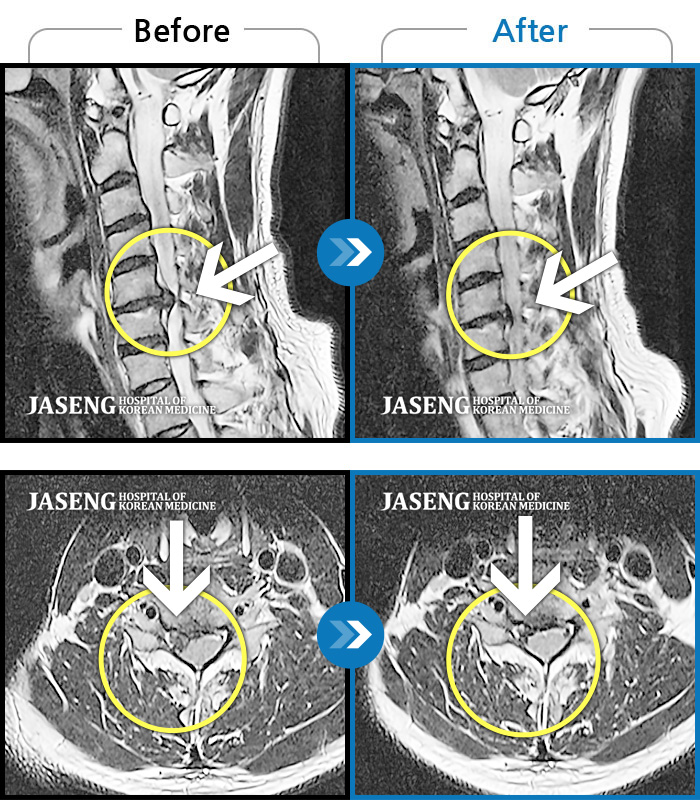

MRI 치료사례

목 통증과 우측 팔로 당기는 통증, 야간통